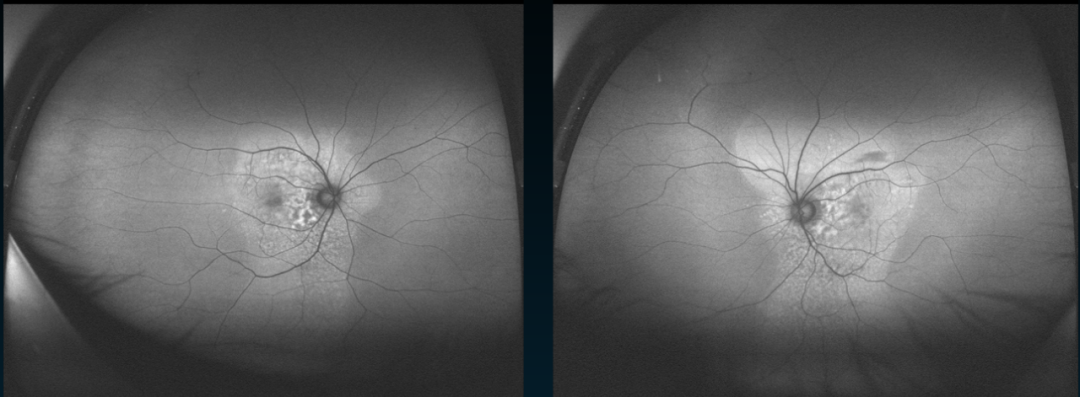

一名29岁的女性,以“左眼视力下降8天”就诊。3年前确诊SLE,并且自述右眼自幼视力差,在对其进行眼部体查时发现,其右眼视力为0.02,左眼为0.4,双眼前节均透明。下面这张图片是其眼底照相的表现,可以看到右眼视网膜血管走行清,左眼黄斑下方积血平面,黄斑未见新生血管,通过荧光血管造影显示颞侧周边视网膜可见新生血管膜伴出血。

双眼眼底照相